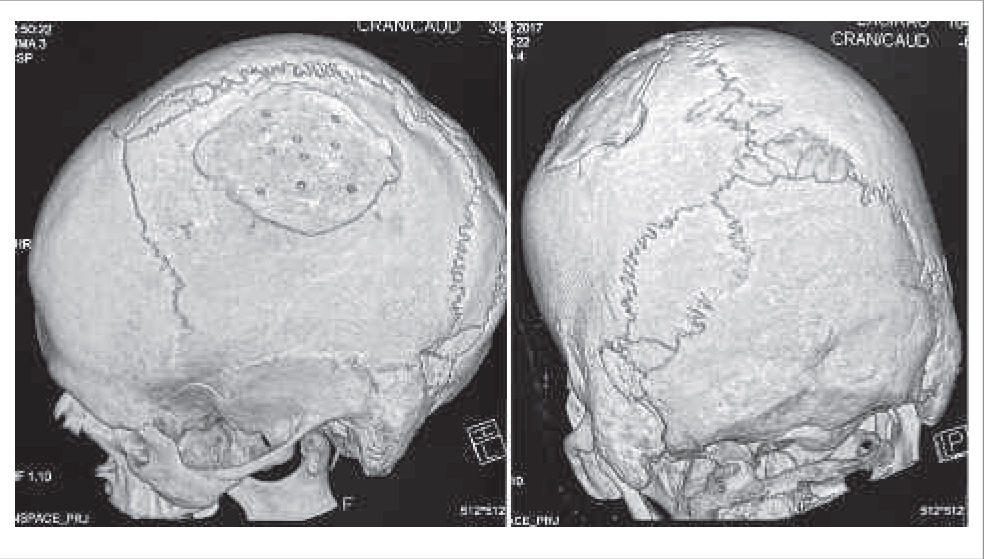

Мультиспиральная КТ черепа пациента позволила увидеть в структуре левой теменной кости костный дефект размером 57х77 мм, закрытый костным трансплантатом без признаков смещения. Однако обращало на себя внимание наличие множественных вставочных костей в швах черепа – кости инков (рис. 3). Кость инков представляет собой вставочную кость, обнаруживаемую по ходу сагиттального и лямбдовидного швов черепа. Они возникают вследствие наличия нескольких центров окостенения чешуи затылочной кости и незарастания швов между ними. Впервые описаны M. Rivero и S. Tschudy в 1851 г. при описании найденных останков в Перу: выявляются у 20% инков. Распространенность в европейской популяции невысока – до 2%. В настоящее время кость инков расценивается как малая аномалия развития, не влияющая на продолжительность жизни пациента [13].

Рис. 3. Данные КТ пациента Г. Примечание. Костный трансплантат в структуре левой теменной кости (слева) и множественные вставочные кости в швах черепа (справа).